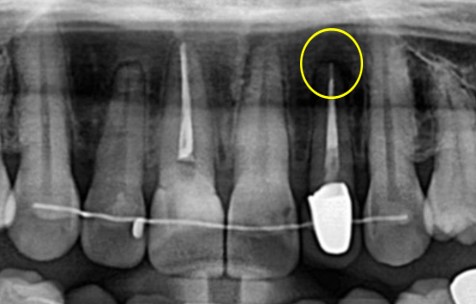

그럼 자세히 보면 뿌리 끝 쪽에 검은 공간이 보이는데 '치근 낭종' 이 있다는 것을 확인할 수 있습니다.

#22 치아는 이미 타치과에서 신경치료 + 크라운 치료가 완료된 치아였습니다.

뿌리 끝 쪽에 물혹이 생기는 것이 ' 치근 낭종'입니다